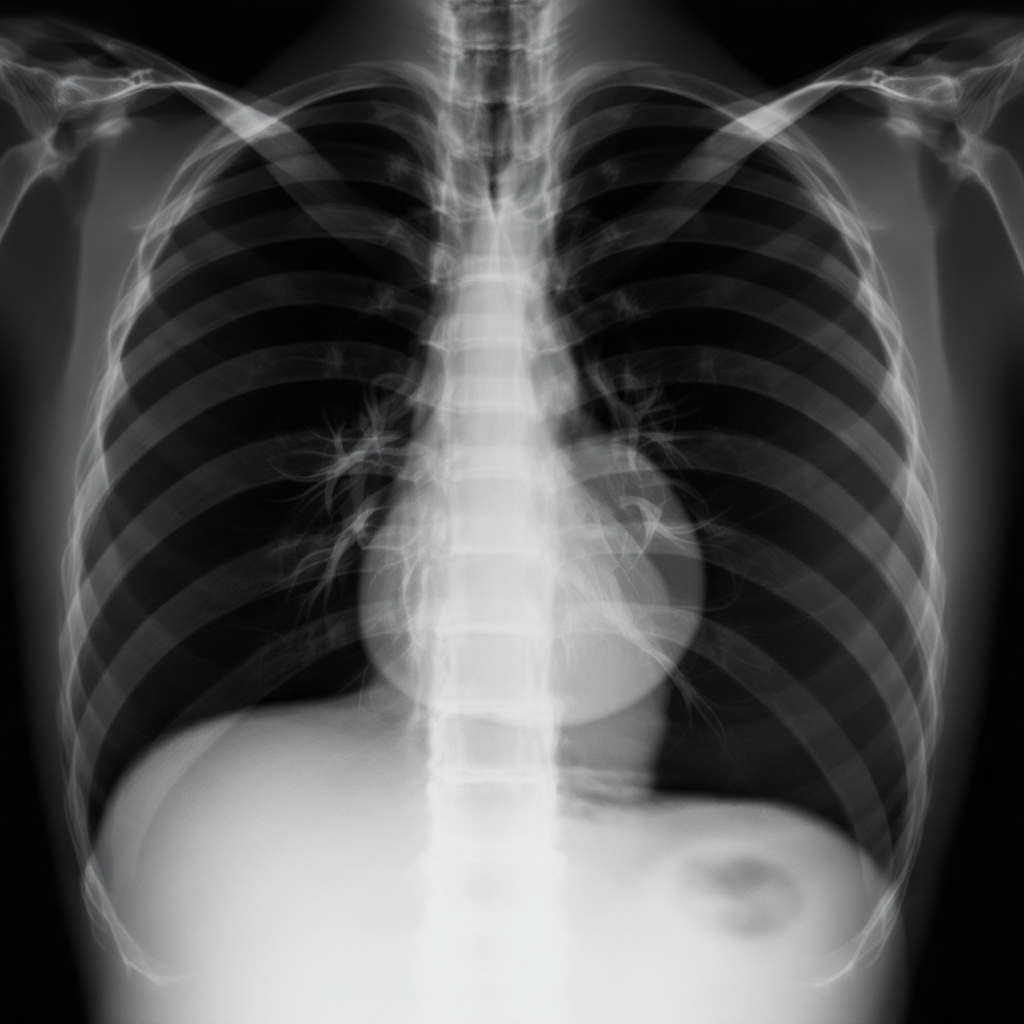

흉부 엑스레이는 의료 영상 진단에서 가장 널리 쓰이는 검사 중 하나예요. 특히 흉부 PA(posterior-anterior)와 AP(anterior-posterior) 촬영 방식은 비슷해 보이지만 실제로는 촬영 위치와 정확도, 용도가 달라요.

흉부 X-ray, 즉 흉부 방사선 촬영은 폐, 심장, 흉막, 늑골, 횡격막 같은 가슴 부위의 구조를 시각적으로 확인하기 위한 가장 기본적이면서도 중요한 영상 진단 도구예요. 전 세계적으로 감기나 폐렴 같은 감염 질환부터 심부전, 기흉, 폐색전증까지 다양한 질병을 진단할 때 쓰여요.

X-ray는 고에너지 전자파를 인체에 투과시켜 신체 내부 구조를 투영하는 방식이에요. 뼈는 단단해서 방사선을 흡수해 흰색으로 보이고, 공기가 많은 폐는 방사선을 그대로 통과시켜 어둡게 보이게 하죠. 이 명암 차이를 통해 내부 장기의 상태를 분석할 수 있어요.

그런데, 같은 흉부 X-ray라도 촬영하는 방향에 따라 결과가 크게 달라질 수 있어요. 바로 그 차이가 PA와 AP 촬영 방식의 핵심이에요. 두 방법 모두 가슴 부위를 찍지만, 방사선이 지나가는 경로와 몸의 위치가 달라서 영상의 품질과 해석 방식에도 영향을 미쳐요.

가령 PA 촬영은 병원에서 서서 촬영할 수 있을 때 가장 이상적인 방식이고, AP 촬영은 환자가 누워 있어야 하는 상황에서 주로 사용돼요. 그에 따라 영상의 왜곡 여부, 심장의 크기, 폐 음영 등에서 차이가 발생한답니다.

PA 촬영은 환자가 방사선 발생기를 등 뒤에 두고, 앞쪽에 필름이나 디지털 검출기를 두는 방식이에요. 이 방법은 X-ray가 등에서 시작해서 가슴을 지나 전면 검출기로 전달돼요. 몸 전체가 자연스럽게 펴진 상태로 촬영되기 때문에 왜곡이 거의 없고, 심장과 폐의 위치도 실제와 비슷하게 나타나요.

반면 AP 촬영은 방사선이 앞에서 들어가고 등 쪽에 필름이 위치해요. 침상에서 촬영하는 경우가 많아서, 환자의 몸이 평평하지 않거나 촬영 각도가 일정하지 않은 경우도 있어요. 이로 인해 심장이 실제보다 커 보이는 경향이 있죠.

심장 크기가 크게 나오면 심비대 같은 질환으로 오해될 수 있어서, 영상 판독 시 주의가 필요해요. 그래서 가능한 경우에는 PA 촬영을 선호하는 이유기도 해요. 또한 폐야의 투명도나 기흉 진단 정확도 등도 PA가 더 우수하다고 알려져 있어요.

흉부 X-ray의 판독 정확도는 단순히 촬영 기술뿐 아니라 촬영 방식에 따라 큰 차이를 보여요. 예를 들어 PA 촬영은 심장의 윤곽과 크기를 보다 정확하게 보여주기 때문에 심장 관련 질환 감별에 유리해요. 특히 심비대 여부나 폐포 음영의 증가 여부를 해석할 때 이점이 많죠.

반면 AP 촬영은 심장이 확대되어 보이기 쉬워요. 이건 방사선이 심장을 먼저 지나가면서 상대적으로 영상에서 그 크기가 부풀려지기 때문이에요. 그래서 AP 촬영만 보고 심장이 커졌다고 판단하면 안 되고, 반드시 다른 임상 지표와 함께 해석해야 해요.

또한 폐의 음영 차이도 중요해요. AP에서는 횡격막이 덜 내려간 상태로 촬영되는 경우가 많아서 폐야가 줄어든 것처럼 보일 수 있어요. 반면 PA에서는 숨을 충분히 들이쉰 상태에서 촬영하므로 폐 야의 투과도가 더 명확하게 나타나요.